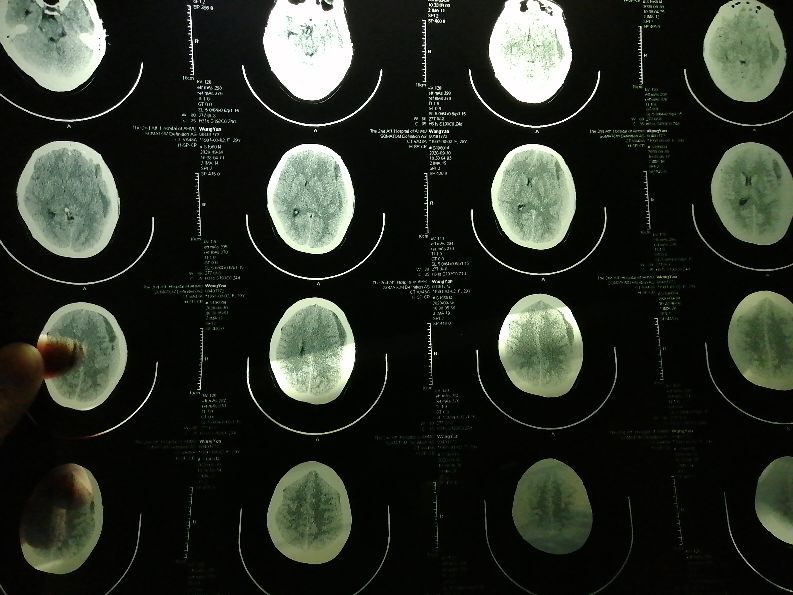

出院一个星期后头又开始疼了,期间对老婆好生照料,夜里根本不让她起来,因为医生说尽量平躺休息。可平躺也解决不了疼痛感,怎么也没也没想到后果这么严重,我也叫老婆去看看,可老婆坚持一个星期实在疼的不行才去的医院,谁又想去医院呢,月子都没出呢!去了医院先问的医生说挂神经内科,神经内科一下开了三个核共磁片子,结果是两天后才能做,因为门诊慢要预约,我问能不能提前做我老婆头疼的厉害,她说不行,得医生开单子才行。那时找医生也下班了,没办法只能等结果出来再来拿片子给医生看,医生直接领着我老婆去神经外科去看了,我那天出差没一起去看,老婆拿出打印出来的单子显示颅内硬膜下血肿,发给我看,我赶紧百度看了一下,好害怕,赶紧打电话就去问。医生看了片子也一顿吓唬我老婆,不能跌倒,不能碰,赶紧叫家人陪同住院啥的。听到这我急忙回去。我怎么也想不明白怎么会出现这样情况,心情很不好。一下是核磁结果图片。

住了院后又拍了一张脑部CT,说是观察,说等脑部血块变成血水才能开刀,我问医生怎么造成的,刚开始问就是说我老婆有没有外力造成的,我们实话实说在医院生产后就这样了,他之后就说什么原因都有可能,总结一句话不知道你是怎么造成的,但是能给你治好!我就笑了,省级最大最好的医院啊,不知道什么原因就去治病吗?!问了其他医生也是三缄其口。不能忍的我打了医患办的电话那时候9月28日,至今已经10天了,也没有给我回复半个电话!当时只是想着治好就行了,只要你们医生用点心就行了。不敢奢求什么。

9月23号住的院,刚进来的时候就说节前可以做手术,进来了又是另一回事了,9月30号又做的CT,说血块还有许多没有变成血水我有点不相信这个医院了,于是10月2号和3号拿着片子就分别去了省立医院和安医一附院,那边的专家都说血块已经化成血水了,可以进行微创手术了,为什么不一样呢,回来后我也没直接给医生说,因为这边医生说头不怎么疼了,可以观察,最好不开刀!因为不开刀是我期望的,所以我沉默了。毕竟在头上开刀。我记得还有一个细节很重要,住院后的第五天吧,找的妇产科医生会诊的,医生没来,不知道什么原因,第二天查房,那个主任医师说我们找人了,我说没有啊,他紧接着就说麻醉科的谁谁谁问了你的病情,会诊的妇产科唉!麻醉科的打电话给神经外科的床位医生,说我们找人了,我想这人肯定是打药的那个人说好话了。是什么原因导致他说好话呢!想想这不是此地无银三百两吗!可后来的事情更是我生气的!

10月7日CT结果

9月30日CT结果